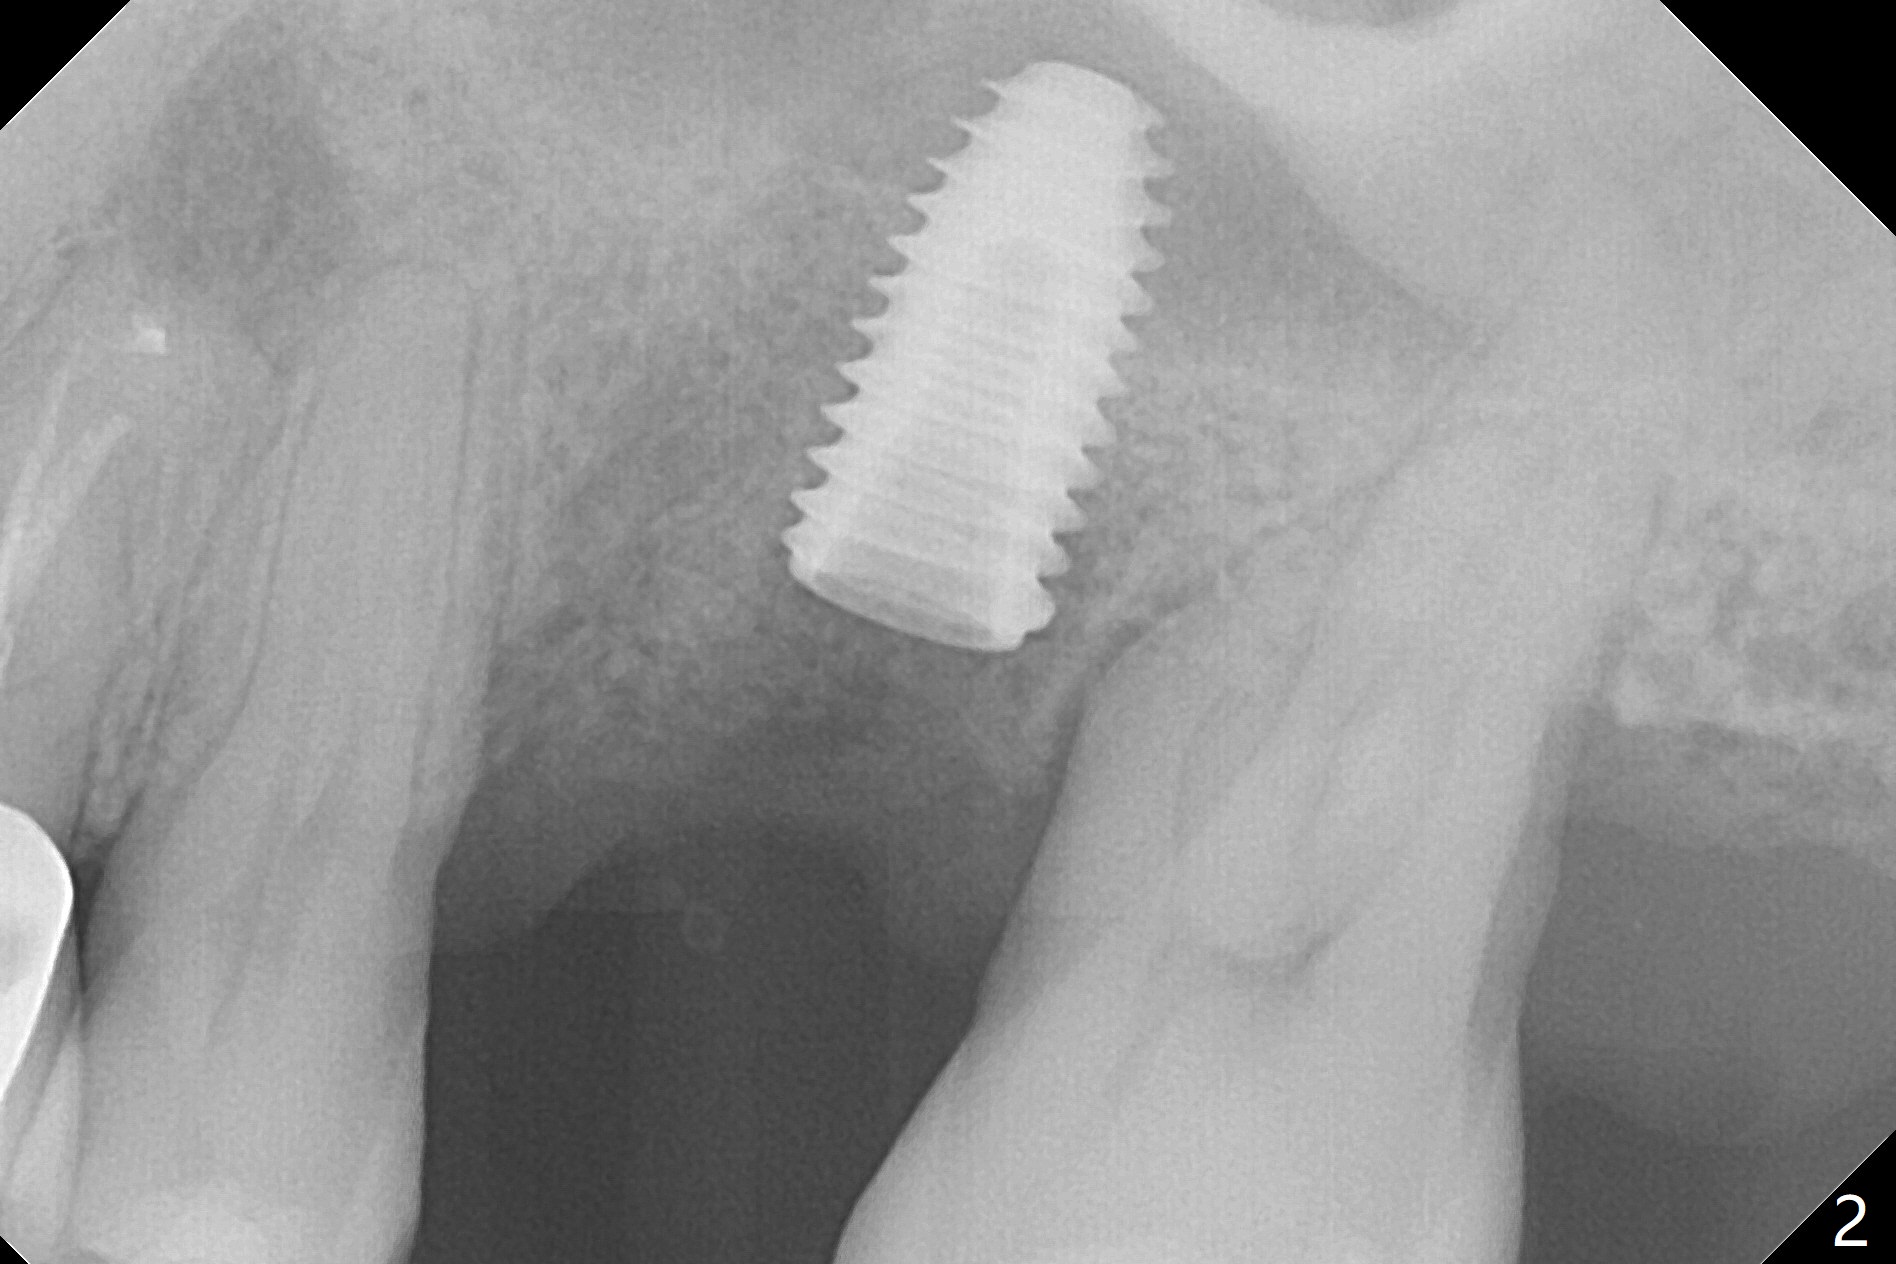

Six months post 2nd placement at #14, the 5x11 mm IBS implant is unstable. The patient smokes a cigarette a day.  After implant removal, the palatal wall of the osteotomy is intact, although low.  With removal of minimal granulation tissue, a 5x10 mm IS dummy implant is placed with stability and slightly subgingival palatal (Fig.1,2).  A 5x8.5 mm definitive implant is placed with ~ 40 Ncm and 3-4 mm subgingival palatal (Fig.3,4).  A 5.7x5.5(5) mm abutment is placed to hold periodontal dressing in place.  If the implant fails again, bone graft should be placed.  The abutment and implant are stable 4.5 months postop (Fig.5); a provisional is fabricated for progressive loading.  The provisional at #14 is narrow mesiodistally, while the tooth #15 is mesially tilted and shifted because of chronic periodontitis and 1 year 4 months of edentulism (Fig.6*).  Limited orthodontics is necessary prior to final restoration.  The 1st step is to raise the occlusion with #14 temporary reline (Fig.7 *); the tooth #15 is distalized initially with a separator, which is inefficient.  It appears that brackets and bands should be placed for distalization.  A month post banding, open coil spring is placed between #14 and 15; with occlusal composite on the opposing tooth (#19) (Fig.8), the tooth #15 is distalized instantly probably related to its periodontal condition (Fig.9 mirror view).  The tooth #15 is further distalized 2 weeks post open coil spring placement (Fig.10).  To act an anchorage, the abutment needs to be torqued with wrench (25-30 Ncm) and the provisional has to be permanently cemented.  The distalization appears to be ~ 1 mm shy 1.5 months post open coil (Fig.11).